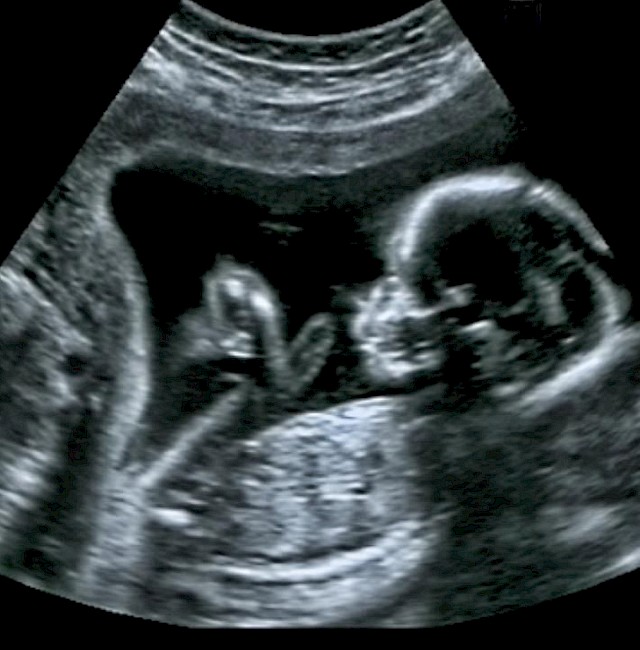

A Durham University's Fetal and Neonatal Research Lab (Egyesült Királyság) által vezetett tanulmányban 100 terhes nőt vizsgáltak 4D ultrahanggal, hogy megnézzék, hogyan reagálnak a születendő babák, miután az anyjuk által elfogyasztott élelmiszerekből származó ízeknek voltak kitéve.